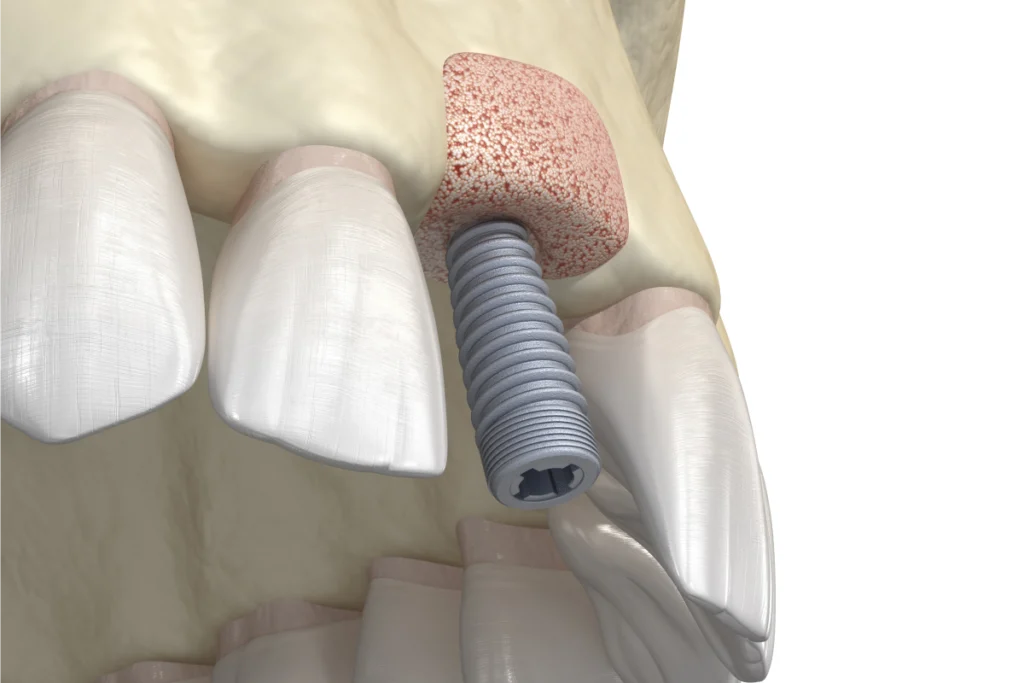

Un implant dentaire est une racine artificielle en titane insérée dans l’os de la mâchoire. Cette racine sert à fixer une prothèse dentaire comme une couronne, un bridge ou une prothèse complète. Il remplace une dent manquante tout en améliorant l’esthétique et la fonction de mastication. Notre chirurgien-dentiste vous accompagne tout au long de ce processus. Chaque étape est réalisée dans le respect de votre confort et des normes de sécurité.

Un implant unitaire est utilisé lorsqu’une seule dent manque. Le chirurgien-dentiste insère un implant dans l’os de la mâchoire et fixe une couronne dessus. Cette solution est idéale pour remplacer une dent unique, qu’il s’agisse d’une molaire ou d’une prémolaire. L’implant unitaire offre un excellent résultat esthétique. La couronne fixée sur l’implant ressemble à une dent naturelle. De plus, cette option conserve la santé des dents adjacentes, contrairement aux ponts traditionnels qui nécessitent parfois de les tailler.

2. Pose de l’implant

L’implant est placé sous anesthésie locale. L’intervention est généralement bien tolérée. La durée dépend du nombre d’implants à poser et de la complexité du cas. Après la pose, une période de cicatrisation est nécessaire. Elle permet à l’implant de s’intégrer à l’os. Cette étape s’appelle l’ostéointégration.